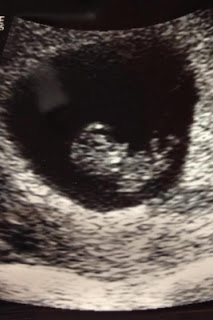

We had our 2nd Dr. Appointment today to make sure all was going well. It was so neat to see you this time because we were able to see your head, legs and arms! You were very active. We saw your arms moving and your legs kicking in the air! The lady who was doing the ultrasound caught a picture with you kicking your legs up!